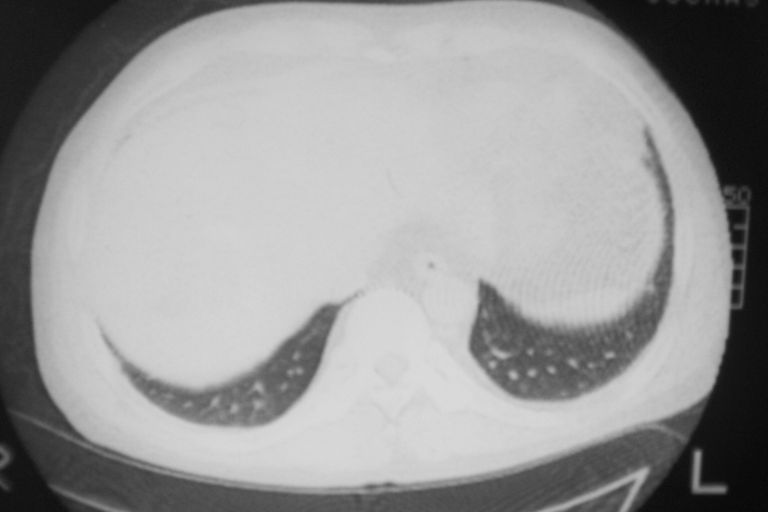

标题: CT10574:男 50岁胸部CT请会诊!

患者 男 50岁 无痛性咯血3天,无其他不适.

1 左肺下叶基底段见两结节软组织密度灶抗炎后复查

2心包积液

2、心包积液

2 心包积液。